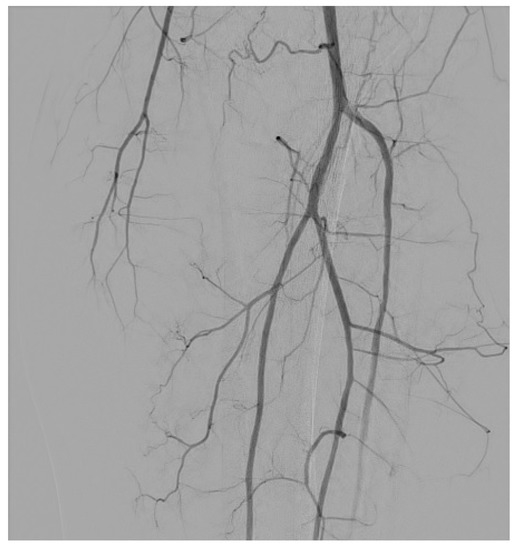

3.1. Stenosis and Occlusion

3.2. Dissection